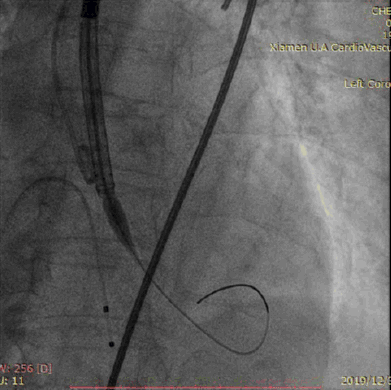

直头导丝跨瓣